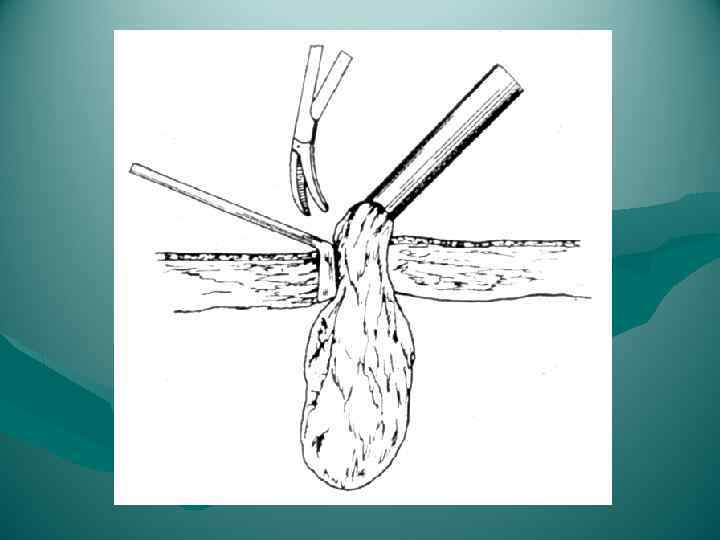

Раздавливание печени

Раздавливание печени

Резекция доли печени

Резекция доли печени